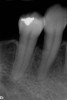

Fig 11. The success and efficacy of this approach was confirmed radiographically at 8 years post-treatment, as demonstrated by the stable gingival margins, thickened biotype with a connective tissue graft, and stable bone levels observed at the first thread of the fixture.

Figure 11

At 8 years post-treatment, implant bone levels were maintained as evidenced radiographically (Figure 11), with stable gingival margins and bone levels at the first thread of the fixture. There was minimal visible damage and scar tissue from the surgical approach to implant placement and tissue grafting to thicken the biotype. Despite the potential challenges, the use of growth factor technology and minimally invasive surgical techniques allowed the esthetic treatment goals for this case to be achieved for the long term (Figure 12).